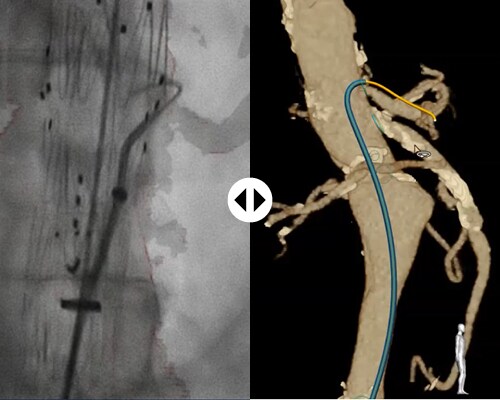

Using light, Fiber Optic RealShape (FORS) technology, exclusive to Philips, enables real-time, 3D visualization of devices1 inside the body without the need for fluoro! FORS-enabled guidewires have a hair-thin optical fiber integrated into them. By pulsing light into the fiber and analyzing the reflections, the full shape of devices can be reconstructed and visualized. These devices are displayed in the context of the patient’s anatomy through overlay on images acquired before or during the procedure, like CT scans and X-rays.

LumiGuide – powered by Fiber Optic Real Shape – gives you unprecedented, full-shape 3D device1 visualization. From any angle. In real-time. With distinctive colors. And integrated into your known roadmap techniques.

FORS technology makes it possible to display the full shape of devices in 3D and in distinctive colors, as opposed to the 2D, greyscale visualization produced by fluoroscopy. FORS images are generated in real-time, and can be rotated and tilted to allow viewing from any angle.